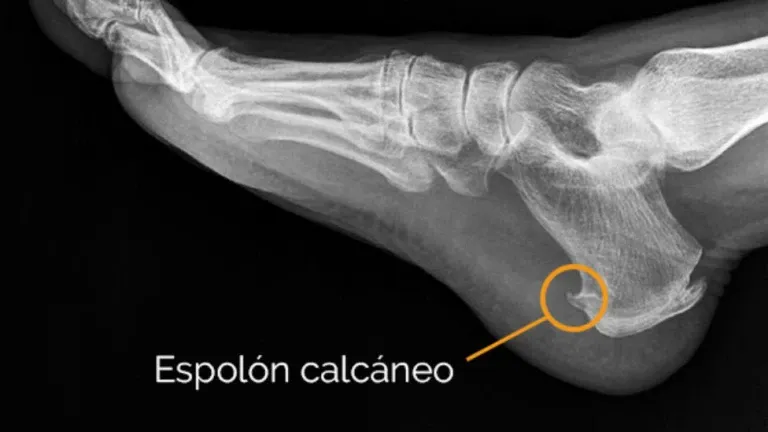

Dolor en el talón por fascitis y espolón calcáneo. Dr. Fernando Ladero